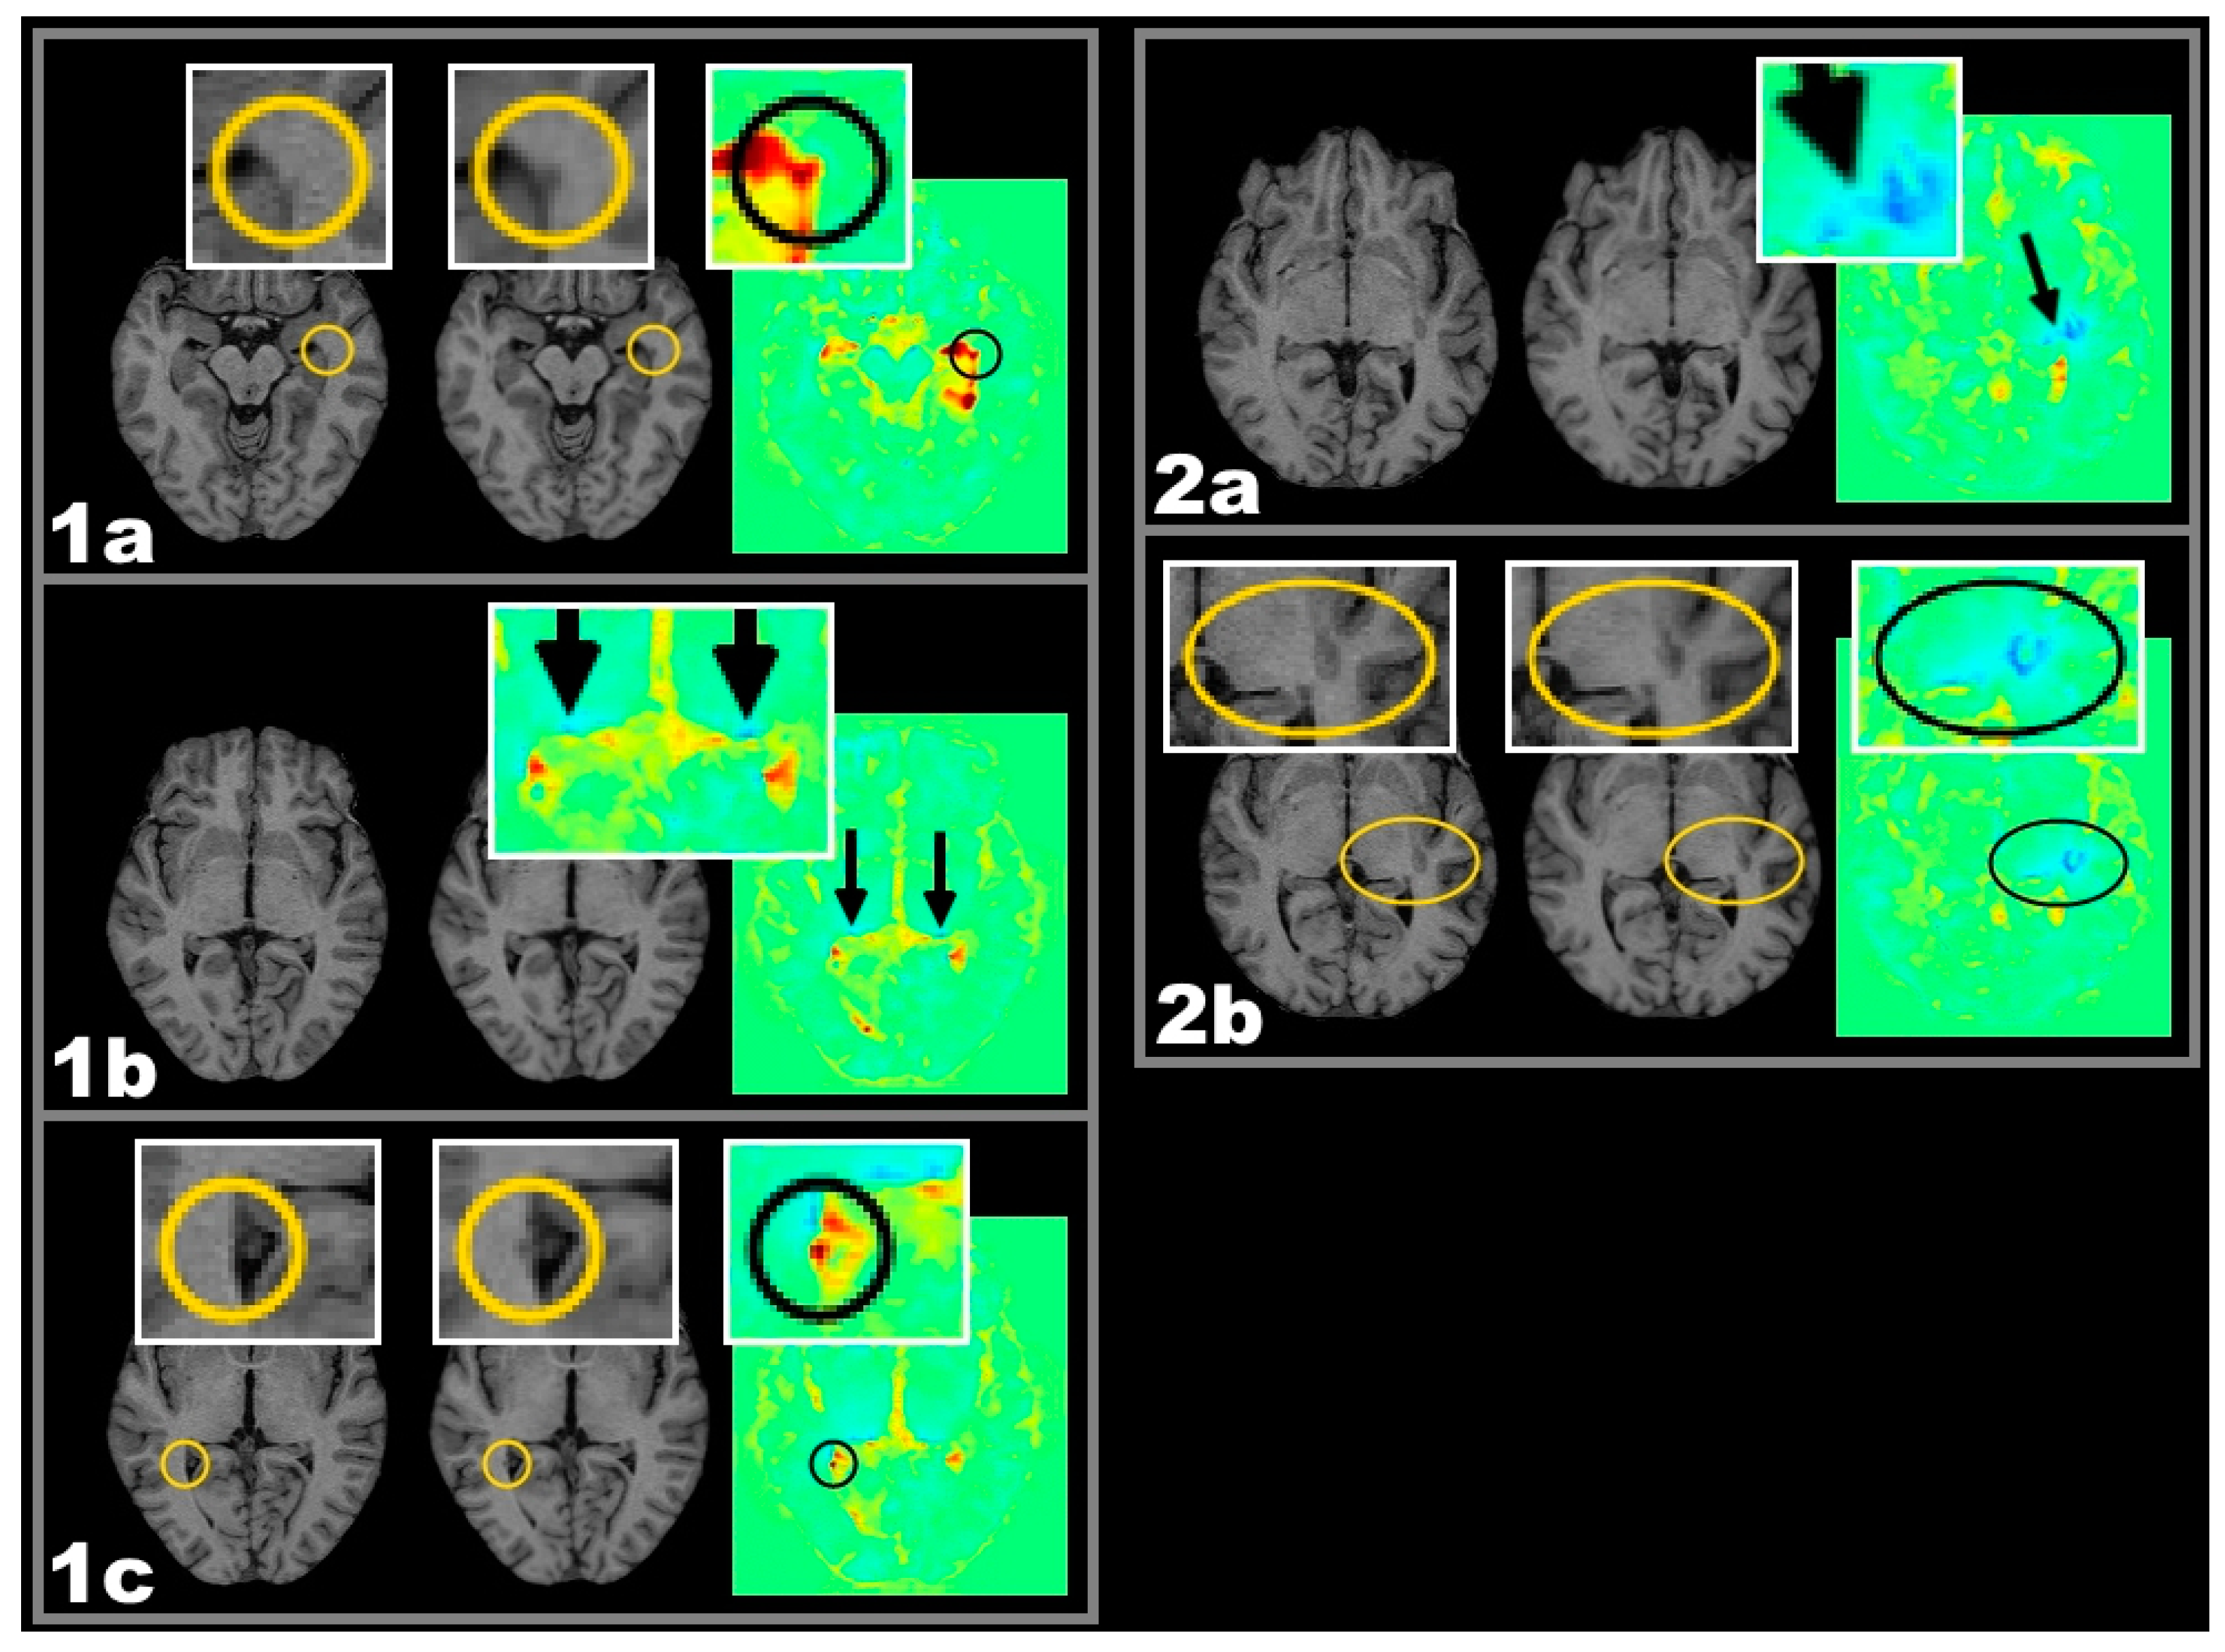

2.2. Lesion-Related Atrophy of the Corpus Callosum and the Lateral Geniculate Nucleus (LGN)

2.2.1. Frequencies of Lesions in Patients with Callosal or LGN Volume Reduction

- Therefore, volume reduction associated with lesions located in anatomical and functional relationship might be explained better by assuming a causal relationship. The spatial lesion-atrophy relation appears to be well in line with the possibility of an underlying causal mechanism. e.g., in both cases of Figure 2, lesion location strongly suggests the lesions to have considerable effect on callosal fibres and callosal shrinkage follows the course of those fibres, which are suspected to be damaged.